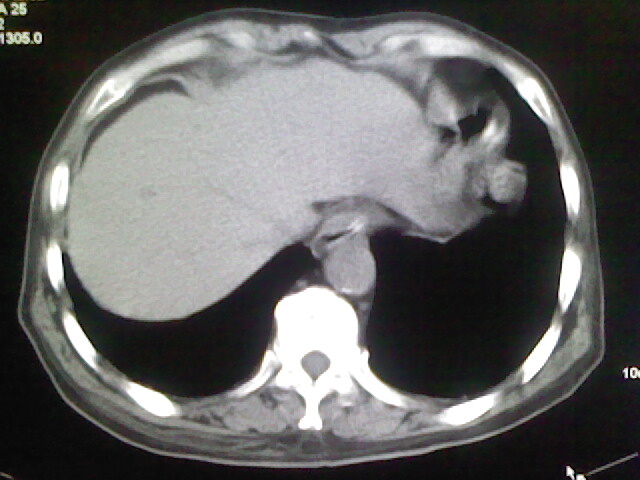

男,70岁,脑出血,长期卧床,左侧背部可触及肿块

慢性间质性炎症,与老年患者长期卧床相关,胸壁软组织及肋骨未见异常。

肺部感染,背部筋膜增厚,考虑坠积性水肿或炎症

右侧肺部见片状密度增高影,边缘模糊。考虑炎症。另食管壁增厚。